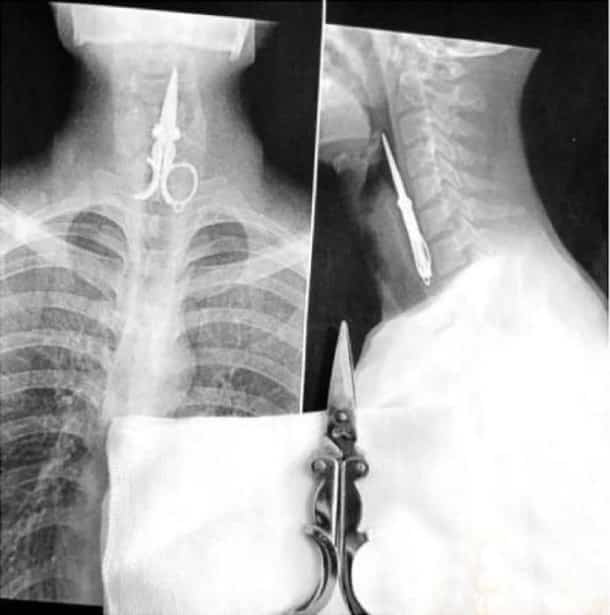

33 radiographies qui prouvent que les gens font des choses douteuses avec leur corps !